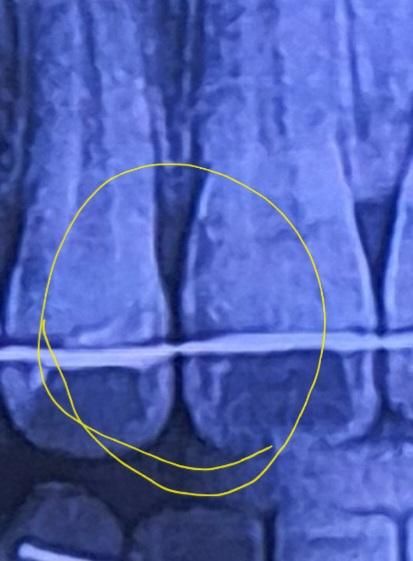

치아와 치아 사이 보이는 검은색은 블랙트라이앵글로 빈 공간입니다. 검게 보이는 것이고, 저 엑스레이에 나타난 투과상과는 별개입니다.

블랙트라이앵글 문제와는 별개로 치아 뒷면이 패여있을 수도 있을 것 같네요